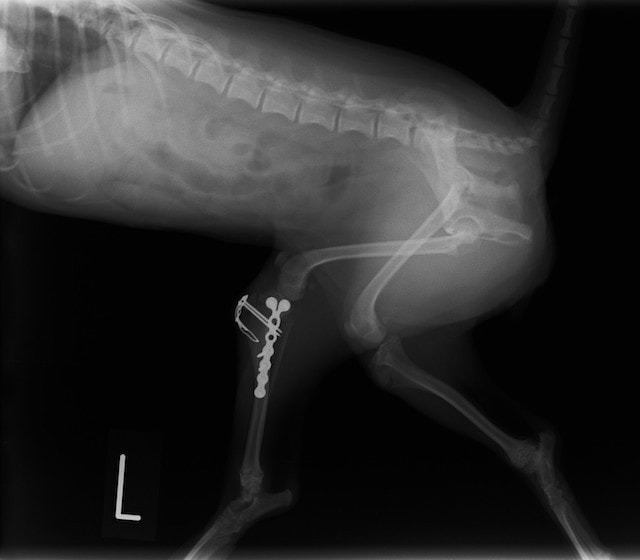

機器

Arthrex社のターゲティングデバイスを用いてピンニングの位置を調整することで、確実な固定を行っています。当院ではこの手術器具以外にも、人の手術にも使用される様々な器具を導入し、手術精度を高め、また医療メーカーと新しい器具の開発、試作にも取り組んでおります。